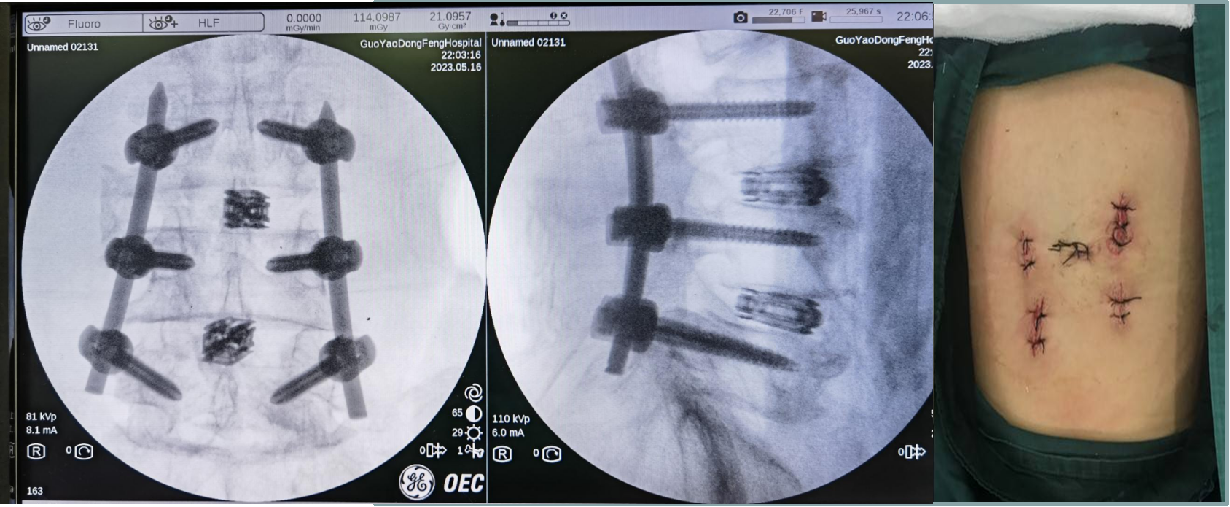

对于脊柱骨折患者,相对于传统的开放性骨折切开复位内固定手术,该手术通过微创技术,经皮小切口进行椎弓根螺钉固定+椎间融合治疗。镜下融合术具有安全可靠、创伤小、出血少、恢复快等特点,患者术后疼痛明显缓解、住院时间短、术后并发症少。